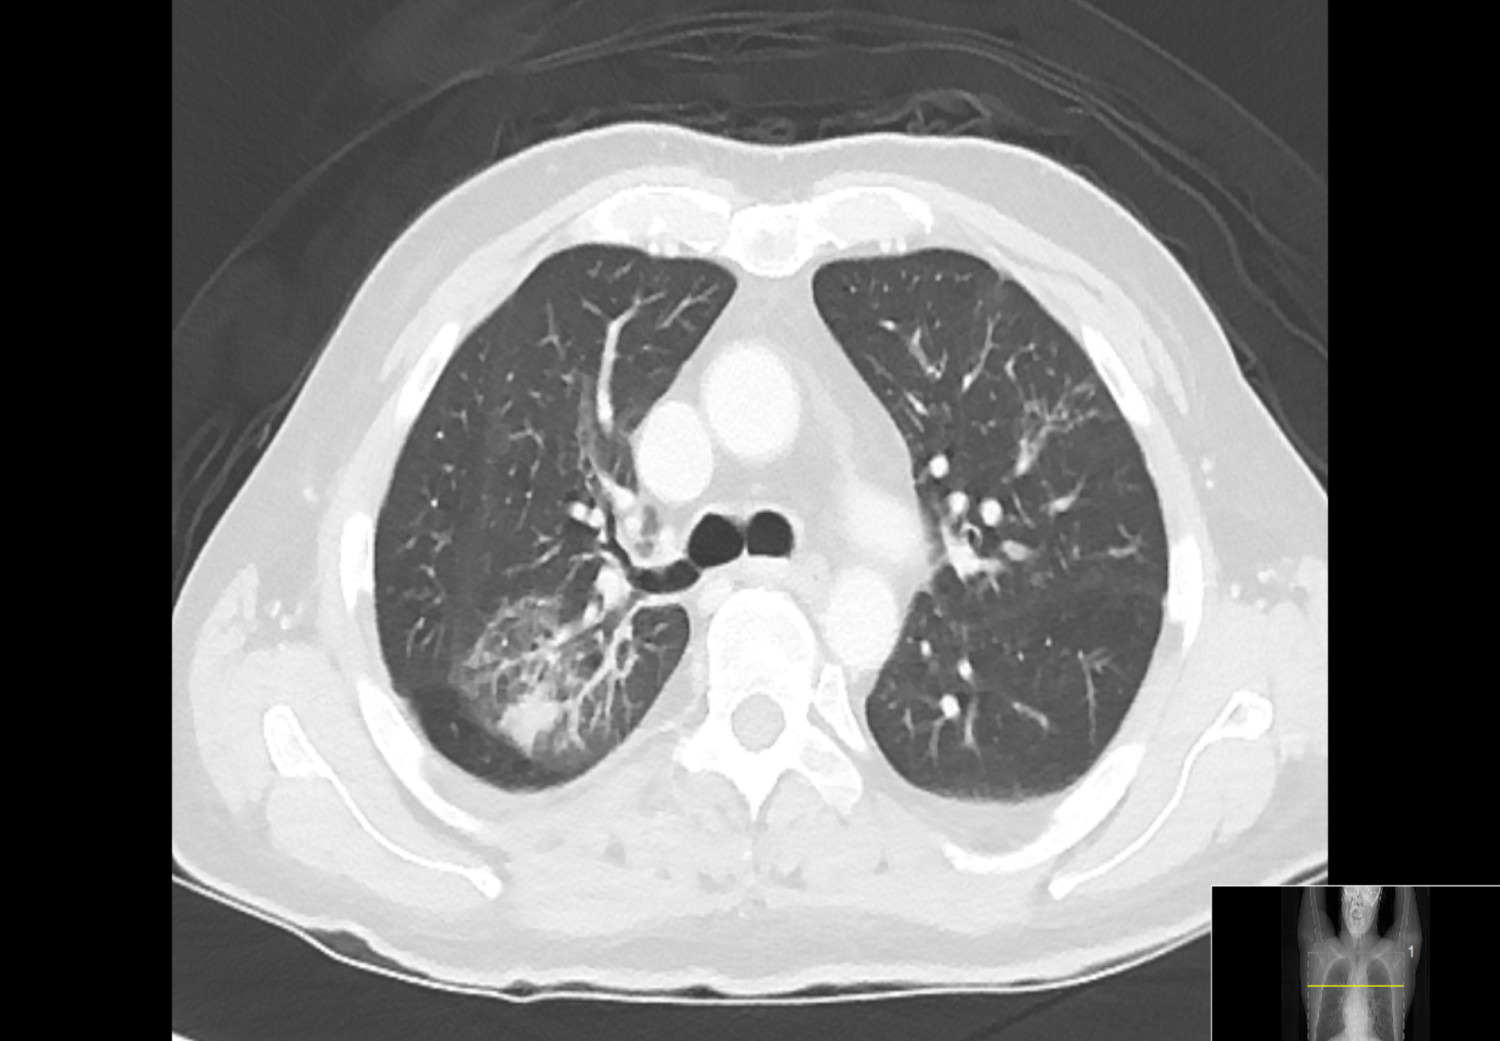

Det ble utført direkte antiglobulintest (DAT, tidligere kalt direkte Coombs’ test). Polyspesifikk («enkel») direkte antiglobulintest var positiv. Monospesifikk («utvidet») direkte antiglobulintest var positiv på C3d og IgG. For å utelukke malignitet, for eksempel lymfom, ble det tatt CT collum, thorax, abdomen og bekken, som kun viste fortetninger i begge lunger, forenlig med infeksjon (fig 2).